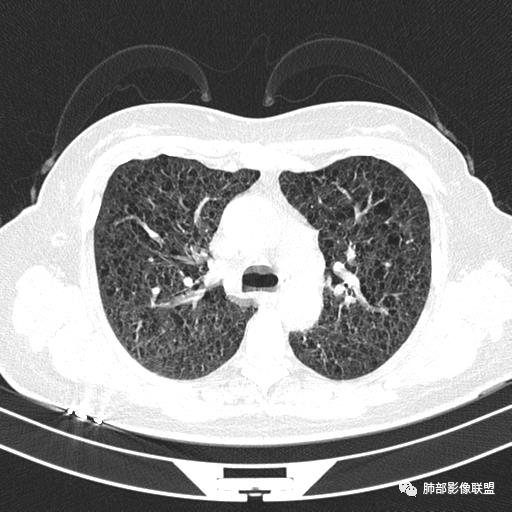

双肺弥漫囊腔,累及肋膈角,囊腔形态相对规则单一。

CT平扫示双肺弥漫分布大小不等囊状薄壁透光区,无内、中、外带分布差异,间质稍示增厚。拟LAM

中年女性育龄期妇女,咳嗽气喘,无吸烟史,有苯吸入史。影像:双肺弥漫均匀小囊腔,无明显分布优势,囊腔形态欠规则,壁薄,部分囊腔边缘血管征,伴双肺弥漫磨玻璃影,无结节,考虑lam,鉴别苯中毒肺损伤,囊腔多有分布优势,小叶中心分布为主,形态规整等

CT表现:双肺弥漫大小不等的薄壁囊腔,囊壁<2mm,外形规则,血管影多位于囊腔周围,囊腔之间肺组织正常,随着疾病进展到晚期,囊腔变大、增多,不可胜数,囊腔可融合成较大的囊,与肺气肿相似,形成间质性肺纤维化。部分病例可出现结节影。